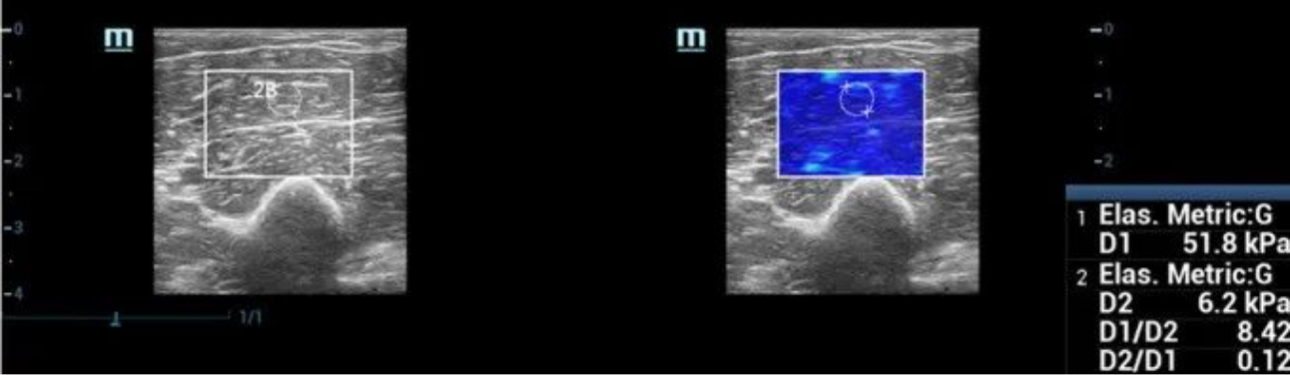

To provide doctors with more confidence, Mindray offers unique Shear Modulus “G” as elasticity metrics tool, besides the Young’s modulus “E” and Shear wave propagation velocity “Cs”. Direction ratio can also be measured with both longitudinal view and transverse view, which is designed especially for the evaluation of anisotropic tissues.

Longitudinal View

pc29-s4@web

Transverse View